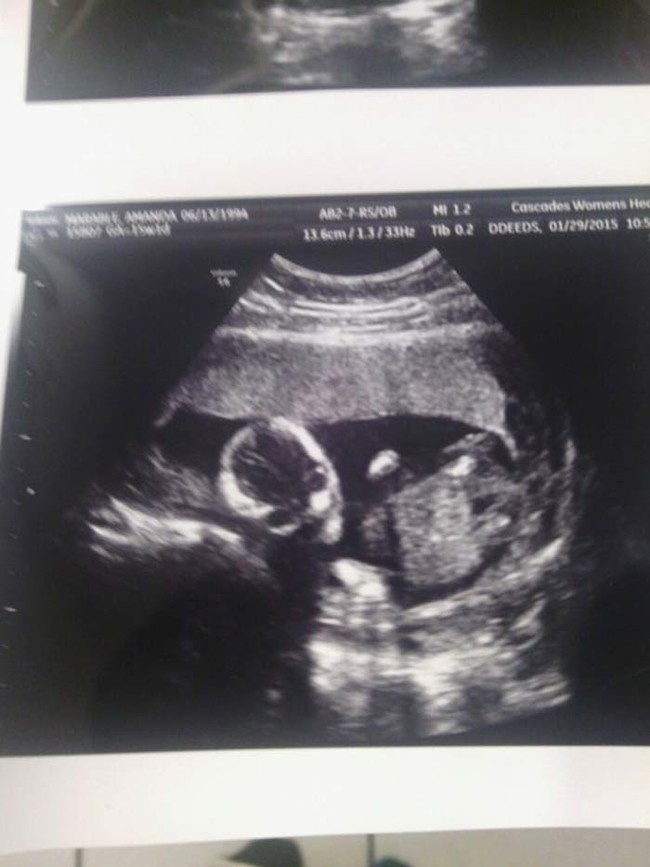

เดี๋ยวนี้ยามตั้งครรภ์คุณแม่เกือบทุกคนก็นิยมอุ้มท้องป่อง ๆ ไปให้คุณหมอทำอัลตราซาวด์ จะได้เช็กดูว่าเจ้าตัวน้อยข้างในอยู่สบายแข็งแรงดีหรือเปล่า แถมยังได้จะเห็นไปหน้าเค้าโครงใบหน้าลาง ๆ ของเจ้าหนูด้วย ดูแค่เงาก็เดาไปกันใหญ่แล้วว่าเหมือนใครมากกว่ากัน จนอดใจไม่ไหวอยากรีบคลอดออกมาให้เห็นหน้าลูกน้อยตัวจริงเร็ว ๆ แต่ถ้ามาเจอ 13 รูปอัลตราซาวด์สุดสยอง ที่เรานำมาฝากจากเว็บไซต์ boredomtherapy เหล่านี้เข้าไปหน่อยล่ะก็... บางทีคุณอาจไม่แน่ใจแล้วล่ะว่า นี่ใช่ลูกฉันจริงหรือเปล่า !!

ถึงจะรักเด็กแค่ไหน แต่ถ้าคุณขวัญอ่อนเราขอเตือนกว่าอย่าเลื่อนลงไปดูดีกว่านะ...